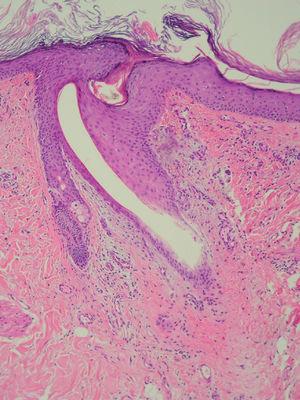

Como exploraciones complementarias se realizaron una biopsia cutánea y una analítica sanguínea. El estudio anatomopatológico (fig. 2) reveló una hemorragia perifolicular y en la analítica se objetivó una anemia normocítica (hemoglobina 95 g/l y velocidad corpuscular media [VCM] 82 fl). No pudieron determinarse las concentraciones de ácido ascórbico en plasma.

Fig. 2.--Extravasación hemática en la dermis, con focos de infiltrado perivascular de predominio linfomononuclear y pelo enroscado, con adelgazamiento focal del epitelio anexial. (Hematoxilina-eosina, x200.)